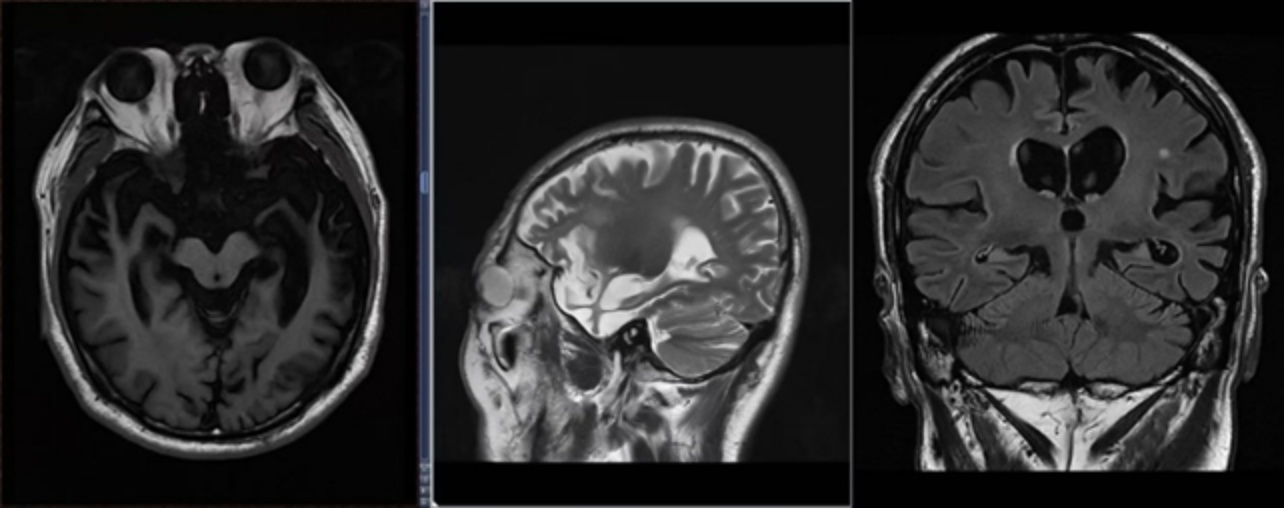

颅脑磁共振(MRI):左侧颞叶脑软化伴周围胶质增生;脑萎缩以双侧额颞叶为著,双侧海马萎缩(右侧MTA 3级,左侧MTA 4级);脑内多发缺血灶(图2),与李秋璇等[5]报道的bvFTD早期影像学特征(额颞叶为主的萎缩)一致。

Figure 2. The bilateral frontal and temporal lobe cortices have significantly thinned, the volume of the right hippocampus has decreased (Grade 3 MTA), and there are old softening lesions in the left temporal lobe

2. 双侧额颞叶皮层显著变薄,右侧海马体积缩小(MTA 3级),左侧颞叶可见陈旧性软化灶